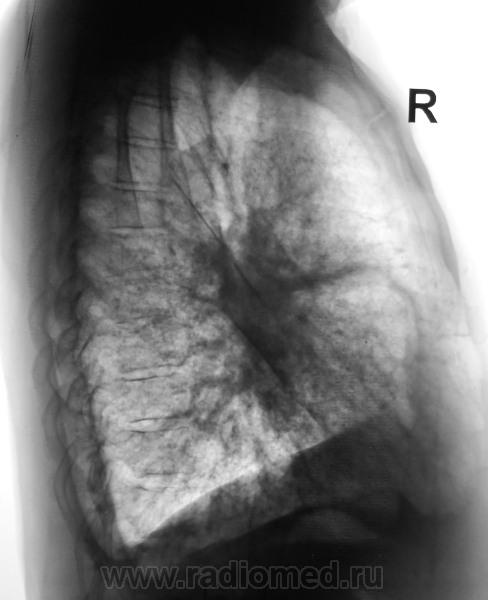

В пользу лимфангита еще преимущественное распространение в средних и нижних отделах, неструктурные корни, еще cuffing (разбухание?) стенки бронхов, подчеркнутость междолевых щелей (на боковом хорошо видно, средняя доля "выделена")